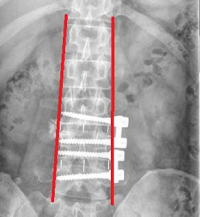

(四)、經(jīng)皮穿刺椎體成形術(shù)(PVP、PKP)

手術(shù)切口4毫米,翌日下地行走。目前已完成經(jīng)皮穿刺椎體成形術(shù)1500余例,患者平均年齡74歲,最高年齡96歲。